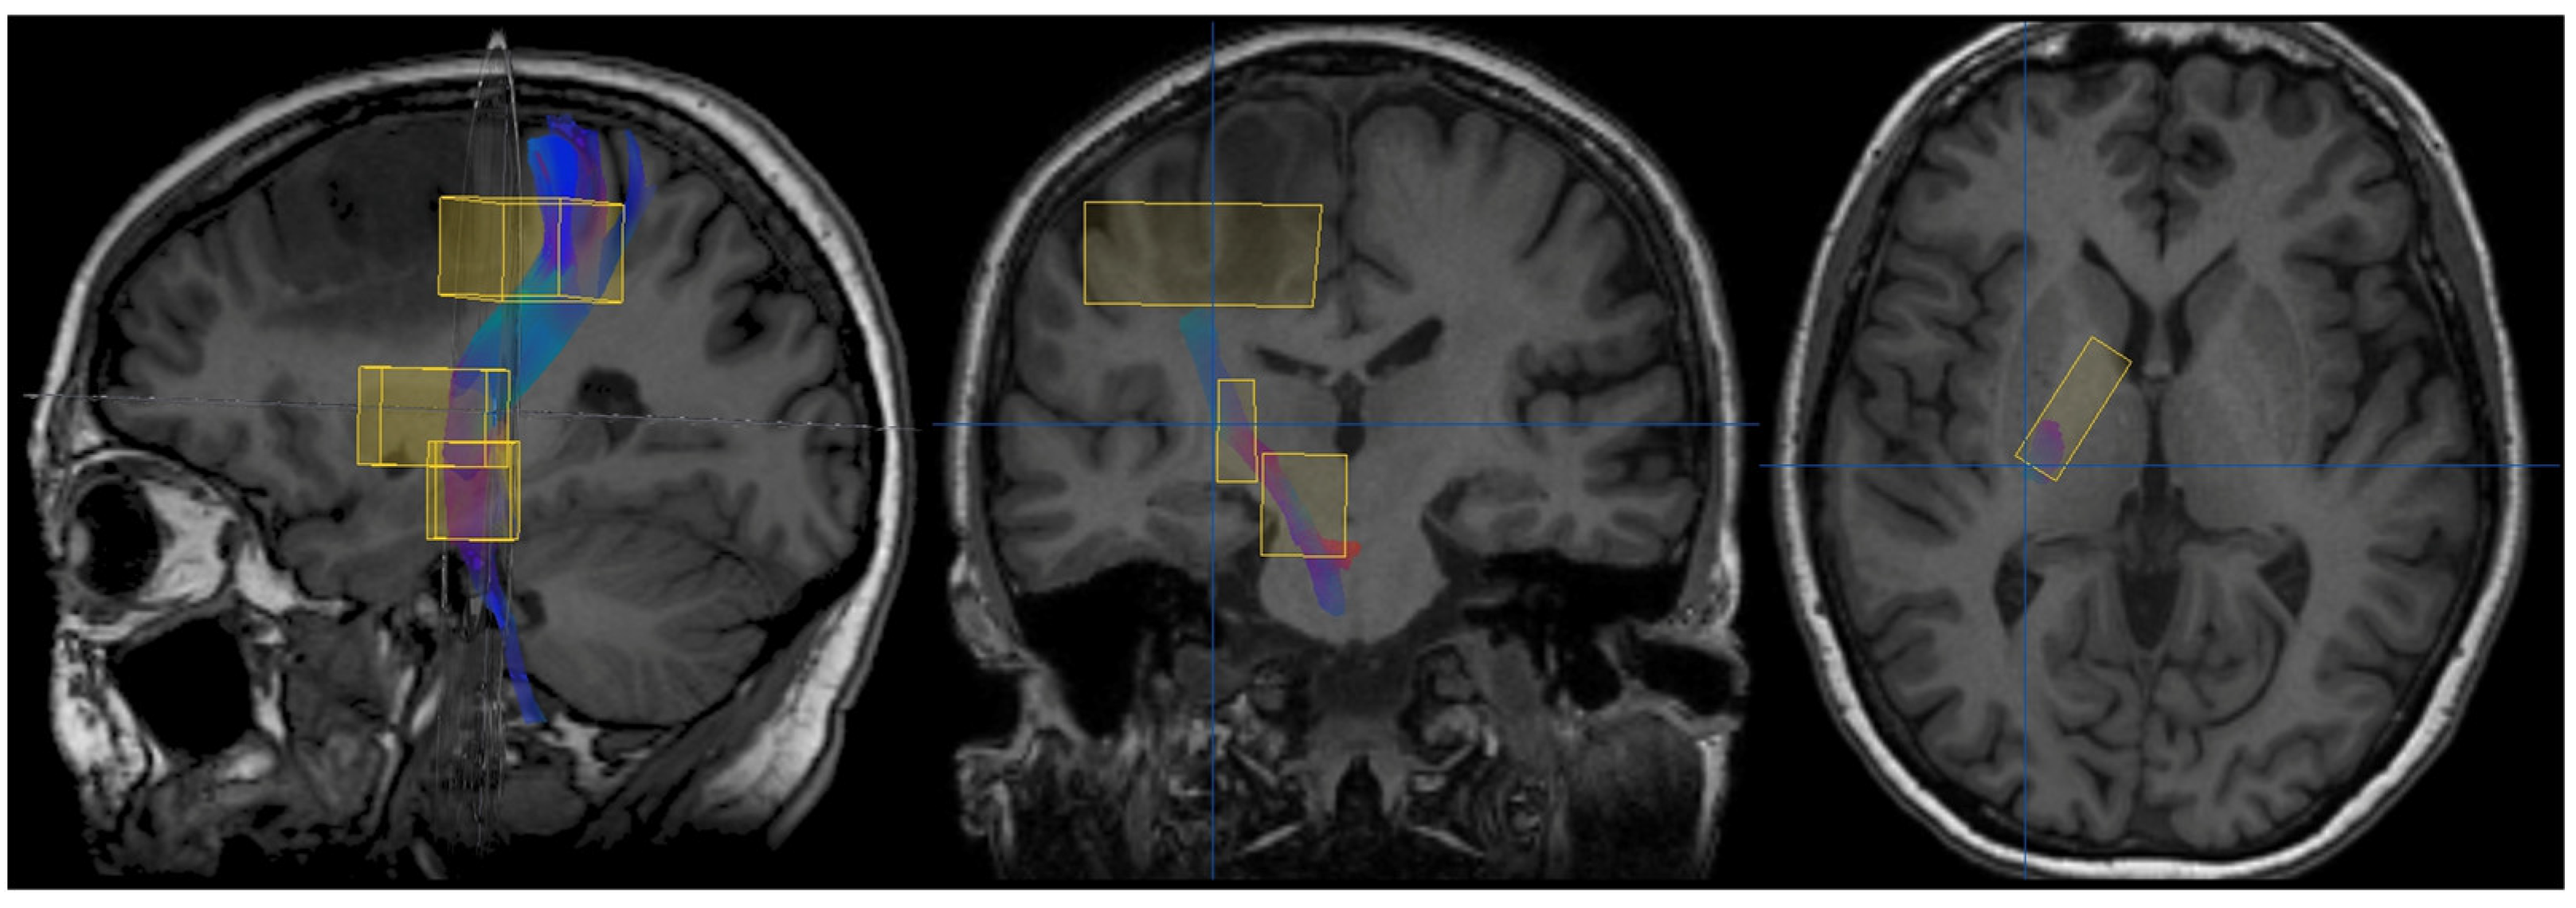

2.1.2. Diffusion Tensor Imaging (DTI)-Derived Tractography

Diffusion images were acquired through SS-EPI with a TR of 6599–8280 ms, a TE of 76 ms, and an FOV of 224 × 224 mm. Images were processed using the software StealthViz with the module StealthDTI (ver. 1.2, Medtronic, Minneapolis, MN, USA). Color-coded fractional anisotropy (FA) maps were created from DTI. The CST was reconstructed on the side of the tumor using multiple cubic regions of interest (ROIs), as shown in Figure 3. Tractography was performed using the iPlan Cranial software (ver. 3.0.5; Brainlab, Feldkirchen, Germany) with an FA threshold of 0.2 and a minimum fiber length of 40 mm.

The resulting CST images were uploaded to the neuronavigation station and helped with the intraoperative recognition of the sub-cortical motor fibers. For this study, the minimum distance between the CST and the lesion was measured on the sagittal view.

Figure 3. CST tractography. The first ROI was placed at the pre-central gyrus, the second ROI at the posterior limb of the internal capsule, and the third ROI at the cerebral peduncle. iPlan Cranial software (ver. 3.0.5, Brainlab, Feldkirchen, Germany).